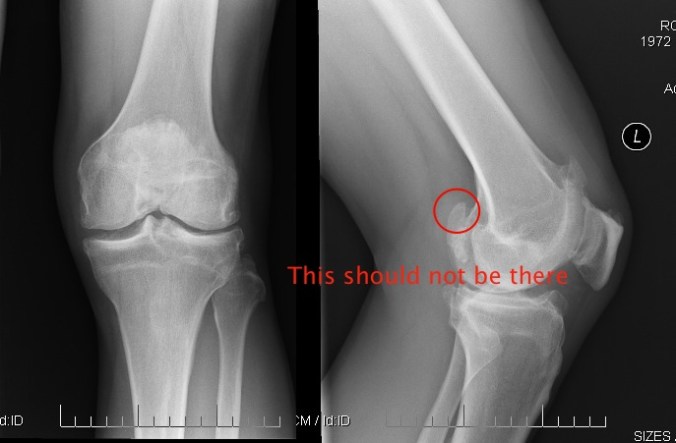

The medial meniscus is normal in morphology. The lateral meniscus however is markedly abnormal. The main body of the meniscus is small and blunted at its medial aspect and there appears to be at least one meniscal fragment within the joint space, not contiguous with the meniscus. Articular cartilages of the lateral joint compartment are also noted to be markedly thinned and irregular.

1. Extensive degenerative changes the knee, much greater than normally expected for age, and greater in the lateral joint compartment with a torn lateral meniscus.

2. Complete tear of the ACLU also is noted.